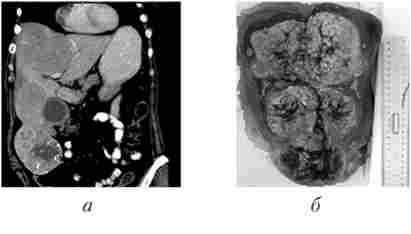

Мал. 16.8. Розширена резекція печінки:

а - комп'ютерна томограма хворий гепатоцелюлярної карциномою; б - віддалений макропрепарат після розширеної правобічної гемігепатектоміі